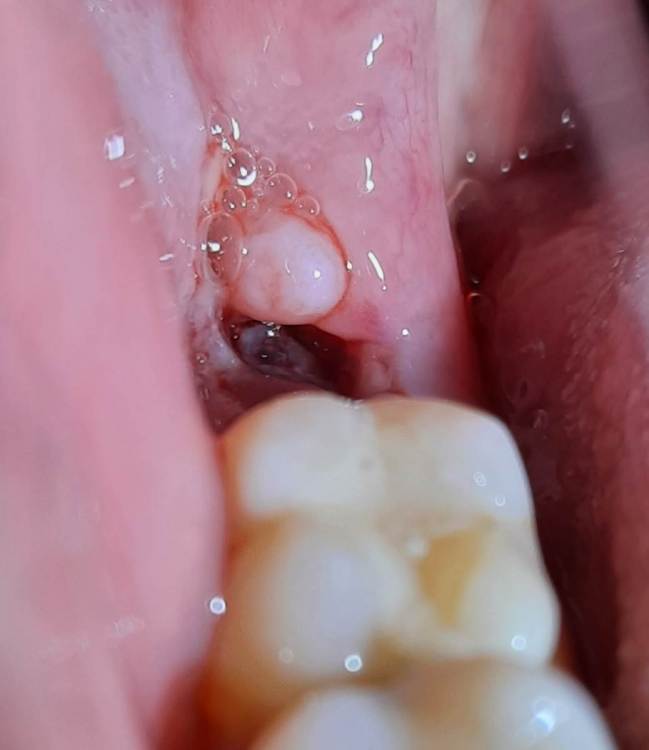

SebaPaseba Опубликовано 13 ноября, 2022 Поделиться Опубликовано 13 ноября, 2022 (изменено) Здравствуйте! Очень нужна ваша помощь/мнение/консультация/совет. Девушка, 22 года. 10.11.2022 в 12:00 мне удалили нижнюю восьмёрку справа (над ней был капюшон из десны и за несколько дней до удаления там произошло воспаление, которое сопровождалось небольшим отёком щеки, сильными болями при глотании, увеличенными лимфоузлами с той же стороны, болью в челюсти и под челюстью). Перед удалением, 08.11.2022 была проведена профессиональная чистка зубов. После удаления врач положил в лунку какую-то мазь и отпустил с миром. Кровь долго не останавливалась, зато боли прекратились очень быстро. Вечером в день удаления челюсть и десны ещё болели от уколов анестезии и от недавнего воспаления, а на следующий день уже всё сошло на нет и болей нет до сих пор. Так же после удаления не было отёка и в целом самочувствие хорошее. Но лунка всё ещё немного кровит (в основном ближе к ночи). В день удаления ничего не предпринимала, поела только спустя часов 8-9, зубы перед сном не чистила. На следующий день после удаления стала делать ванночки с хлоргексидином и осторожно чистить зубы. Поднималась ненадолго температура до 37/5. Вчера в лунку попал кусочек еды. Я пыталась его вымыть водой (не полоская, а просто наклоняя голову то в одну то в другую сторону), но это не помогло и кусочек лишь сдвинулся из центра к краю лунки. Оставлять его там я побоялась, чтоб не спровоцировать инфекцию, и максимально осторожно достала зубочисткой, почти не прилагая усилий, чтоб не повредить сгусток. Сразу после этого всё было хорошо, но спустя некоторое время (полчаса-час) лунка снова начала кровить. Сегодня там чётко видно какое-то белое образование, похожее на кусочек еды. Эта штука была там и вчера (ещё до попадания еды в лунку), и она с каждым днём как будто становится больше. Я не понимаю, это нормальный процесс заживления или нужно начинать беспокоиться? Очень боюсь, что это альвеолит. Прямо сейчас, кажется, присутствует не очень приятный запах изо рта (но не сказать, что прям гнилостный). Лимфоузлы под челюстью всё ещё слегка увеличены, но не болят. Лунка вновь кровит немного. Боли полностью отсутствуют, иногда бывает ощущение пульсации. Температура 37/3 (не знаю, от воспаления или нервов, просто я ОЧЕНЬ СИЛЬНО нервничаю последние дни). К врачу смогу попасть в лучшем случае только завтра, а паниковать начинаю уже сейчас. Пожалуйста, посмотрите и скажите, может ли это быть отклонением? 1 фото - состояние вечером 11.11.2022 2 фото - состояние вечером 12.11.2022 3 фото - состояние сейчас 13.11.2022 Изменено 13 ноября, 2022 пользователем SebaPaseba Ссылка на комментарий

SebaPaseba Опубликовано 13 ноября, 2022 Автор Поделиться Опубликовано 13 ноября, 2022 @Irouil спасибо за ваше мнение. Немного успокоили. Особенно по поводу кровоточивости. Боли иногда бывают, но они очень редкие и слабые. Списываю это скорее на естественные последствия после удаления. А насчёт белого образования - это может быть фибрин? И нормально ли, что он выглядит как шарик? Просто видела на сайтах информацию, что он вроде как образуется по всей поверхности лунки в виде налёта Ссылка на комментарий